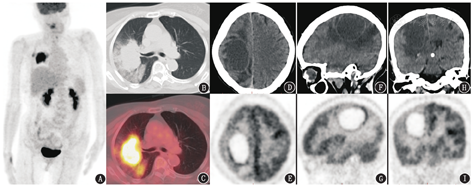

病例1 患者女,75岁,2周前无明显诱因出现左侧肢体定位感减退,当地医院脑MRI提示:右侧顶叶中线旁占位,考虑转移瘤合并出血可能。为进一步评估脑占位性质、寻找潜在原发灶,患者行18F-脱氧葡萄糖(fluorodeoxyglucose, FDG)PET/CT(德国Siemens公司Biograph64 Truepoint TrueV)显像(图1),可见右侧肺门区摄取异常增高肿物,大小为7.2 cm×4.5 cm,最大标准摄取值(maximum standardized uptake value, SUVmax)为8.3,肿物致右肺上叶支气管截断,远端见斑片及磨玻璃影的阻塞性改变;右侧额顶叶囊性占位,大小为5.5 cm×3.4 cm,囊腔呈放射性缺损区,囊壁菲薄且厚薄较均匀,放射性摄取明显高于白质,SUVmax为5.0,病变周围大片状水肿带,相邻额顶叶皮质代谢减低,左侧小脑代谢亦减低,中线结构略向左移位。

该2例患者有相似之处,脑占位均以囊性为主,囊壁代谢明显增高,周围伴明显水肿,且均发现肺占位,首先要考虑和排除的就是肺癌伴脑转移瘤。病例1 PET/CT图上见右肺门区代谢增高肿块,伴支气管包绕截断和远端肺野阻塞性改变,符合肺癌的典型表现。若肺癌诊断明确,那么颅内病变为脑转移瘤的可能性很大,但仍需根据影像所示对颅内占位进行分析。由于脑组织缺乏淋巴系统,脑转移瘤几乎均来源于血行转移,其分布受脑血液供应特征影响,好发于大脑半球的皮质、皮质下,尤其是皮髓质交界区,可呈圆形、卵圆形、环形,可伴有明显水肿,水肿通常局限于白质区,保留覆盖的皮质。本例颅内占位位于右侧额顶叶皮质下,呈环形,代谢不均匀增高,周围伴有明显水肿,也符合脑转移瘤表现,因此临床有把握诊断为肺癌伴脑转移瘤。需要注意的是,由于大脑皮质高代谢的影响,且有的脑转移瘤由于囊变、出血等导致实性成分较少,在PET上FDG的高代谢可能不明显,需结合脑MR加以判断,并且要警惕PET/CT可能遗漏小转移灶的可能。